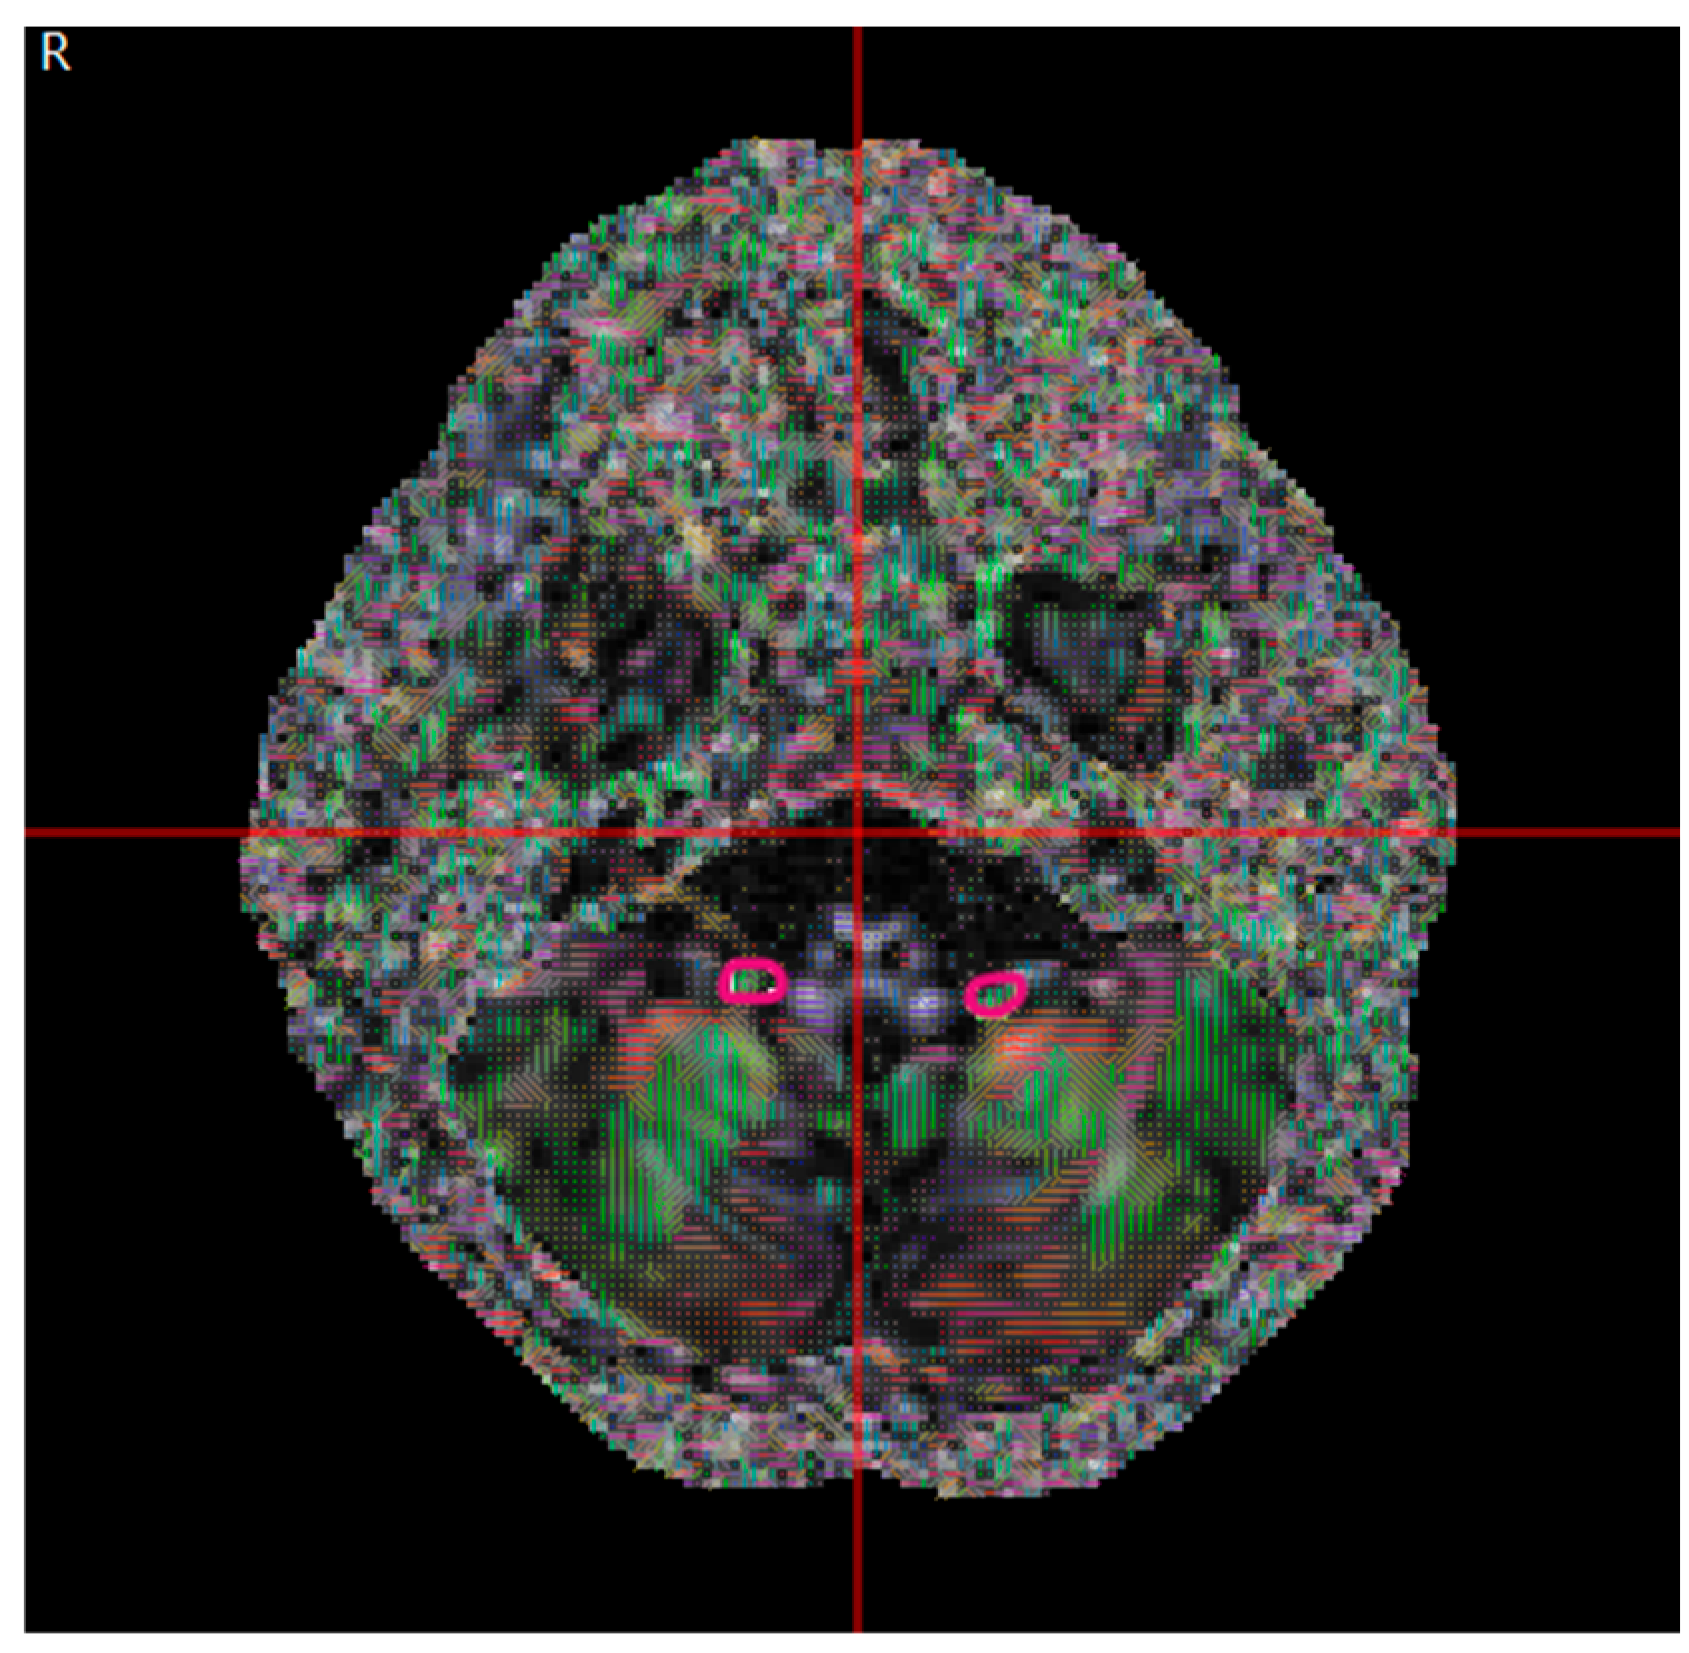

2.2. Data Collection

2.3. Basic Theory of DTI Metrics

2.4. Data Analysis